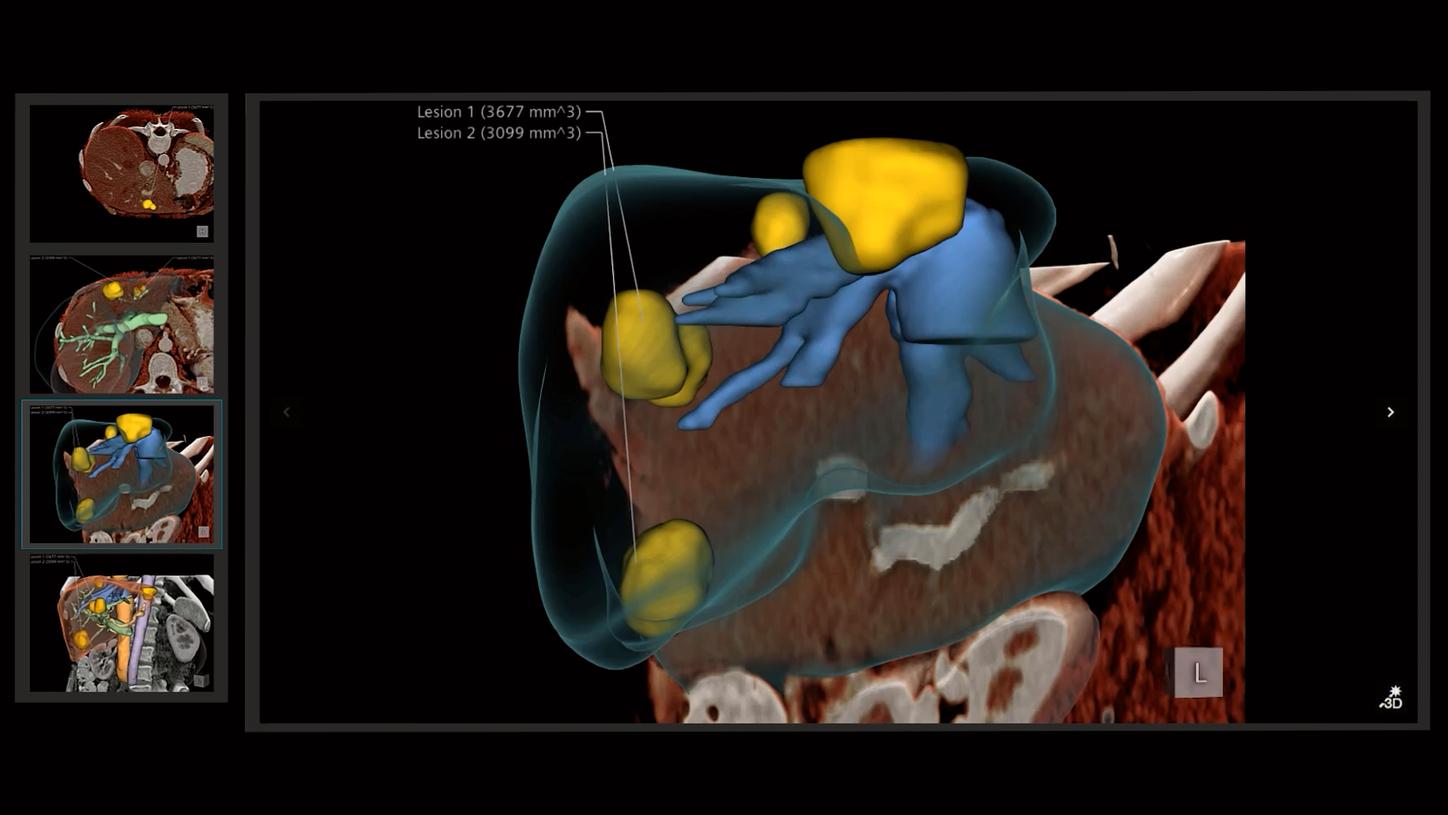

In the area of surgical guidance, for example, they use computer graphics for minimally invasive surgery, such as laparoscopic procedures. “We generate overlays using computer graphics techniques that synthesize patient data, pre-operative data, and planning data, and display it on top of the video feed in such a way that we can help the surgeons do a better job,” Kal explains. “And by using the correct depth visualization techniques, we allow them to see 3D structures in ways they could not before.”

Another field of application is education and training. Here they also use techniques from the movie industry to create photorealistic renderings of patient cases. The idea is to train future doctors and clinicians using actual patient- and disease-specific data. Another field that is a focus of Kal and his colleagues: They want to use 3D image visualization to support dialogue with patients by allowing physicians to communicate information about the disease in a more illustrative way.